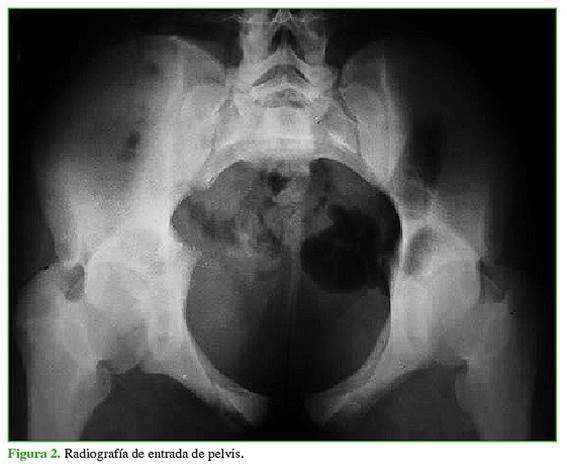

Las fracturas se clasificaron, según la clasificación de Young y Burgess, en las radiografías panorámica (Figura 1), de entrada (Figura 2) y de salida de pelvis (Figura 3), y tomografía computadorizada.